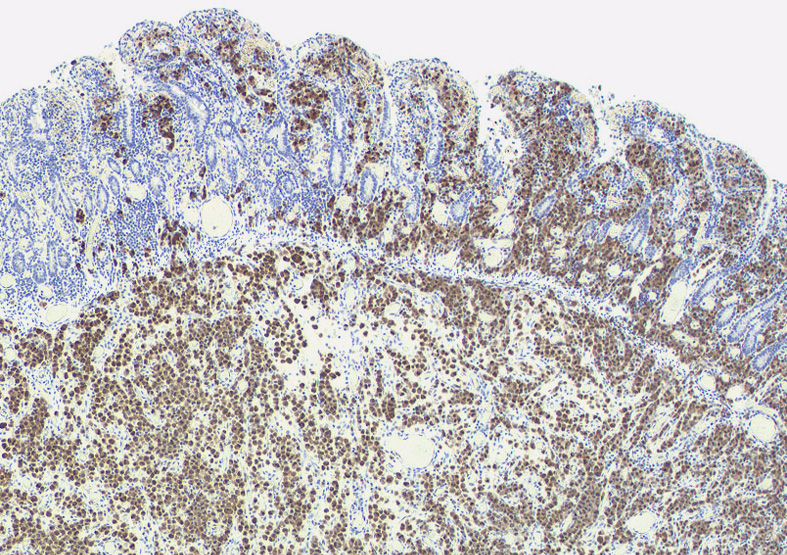

免疫染色-ALK

ALKloupe.jpg

ALK01ICH.jpg

ALKALK